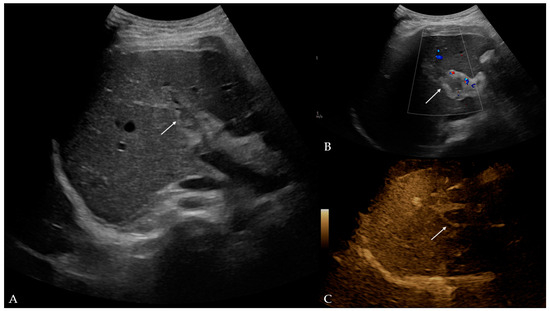

Twelve days later, the patient presented to the ED with a two-day fever (38 °C) and no other symptoms. The postoperative scar and ileostomy were unremarkable, and no signs of peritonitis were detected on clinical examination. Laboratory blood tests showed leukocytosis [15.56 (3.4–9.7 × 109/L)] with neutrophil predomination [10.99 (2.06–6.49 × 109/L)] and elevated liver enzyme [AST 63 (11–34 U/L), ALT 153 (8–41 U/L), GGT 220 (9–35 U/L), ALP 185 (54–119 U/L)] and CRP levels [99.6 (<5 mg/L)]. Other parameters were within the normal values. The attending surgeon referred the patient to the transabdominal US under suspicion of fluid collection. The US and color Doppler (CD) analysis showed left portal vein thrombosis and preserved patency of the hepatic arteries, veins, and inferior vena cava (Figure 1). No free fluid or collection was found. The patient was then referred to contrast-enhanced abdominal and pelvic CT to evaluate the extent of the thrombosis (Figure 2). The left branch of the portal vein was occluded entirely, and the segmental branch of the right portal vein was partially occluded. Thrombotic content was also found in the inferior mesenteric vein. No free fluid, collection, or liver and bowel perfusion abnormalities were found. Due to the described findings and recent diverticulitis, pylephlebitis was the imaging diagnosis. The patient was admitted to the hospital and put on low-molecular-weight heparin (LMWH) and intravenous administration of antibiotics (meropenem).

Figure 1.

Ultrasound and color Doppler of liver with addition of B-flow option: (A) B-mode—hyperechogenic material in lumen of left portal branch, potentially indicative of thrombus (arrow); (B) color Doppler—no Doppler signal in left portal branch, which corresponds to thrombus (arrow); (C) B-flow—no flow in left portal vein, which confirmed earlier findings (arrow).